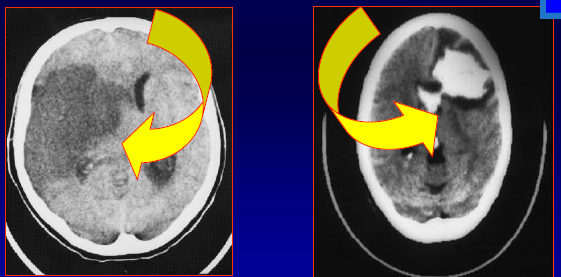

מהו הממצא שבתמונה

חסימה מלאה של ה

MCA

עם דחיקה של המיספרה ימין